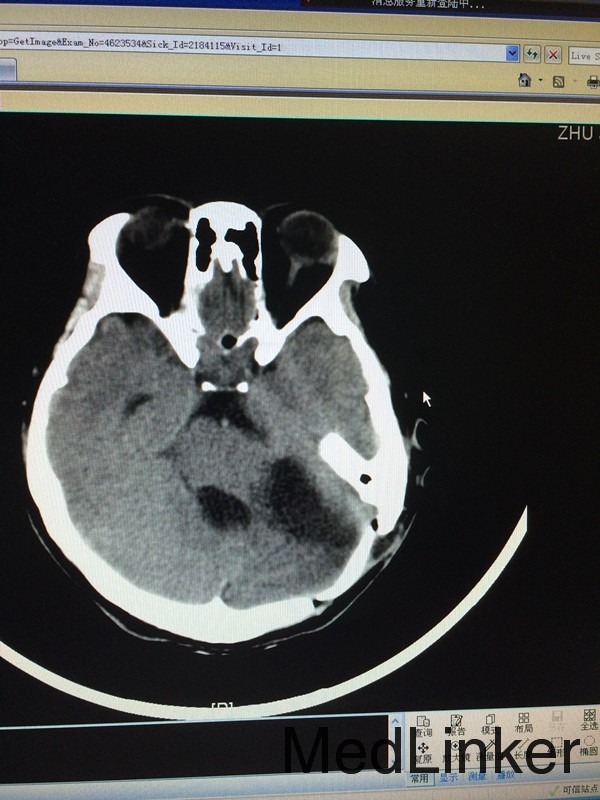

主诉:头晕头痛5月余,伴听力下降视物模糊3个月 病史:患者28岁女性,于5个月前无明显诱因出现头痛头晕,3个月前出现视物模糊,伴耳鸣,于外院行头颅MRI提示:左侧桥小脑角区占位,考虑听神经瘤。

查体:左侧轻微面瘫,左侧面部感觉稍减退,余无特殊 辅助检查:头颅CT提示左侧桥小脑角区类圆形肿物,考虑听神经瘤可能,四脑室受压变窄并右移

诊断:左侧听神经瘤 治疗:行左侧桥小脑角区占位切除术,术后病理提示左侧桥小脑角神经鞘瘤